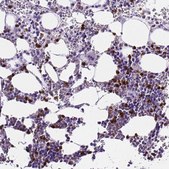

immunohistochemistry: 1:500-1:1000

The Human Protein Atlas project can be subdivided into three efforts: Human Tissue Atlas, Cancer Atlas, and Human Cell Atlas. The antibodies that have been generated in support of the Tissue and Cancer Atlas projects have been tested by immunohistochemistry against hundreds of normal and disease tissues and through the recent efforts of the Human Cell Atlas project, many have been characterized by immunofluorescence to map the human proteome not only at the tissue level but now at the subcellular level. These images and the collection of this vast data set can be viewed on the Human Protein Atlas (HPA) site by clicking on the Image Gallery link. We also provide Prestige Antibodies® protocols and other useful information.

- immunohistochemistry

- IHC tissue array of 44 normal human tissues and 20 of the most common cancer type tissues.